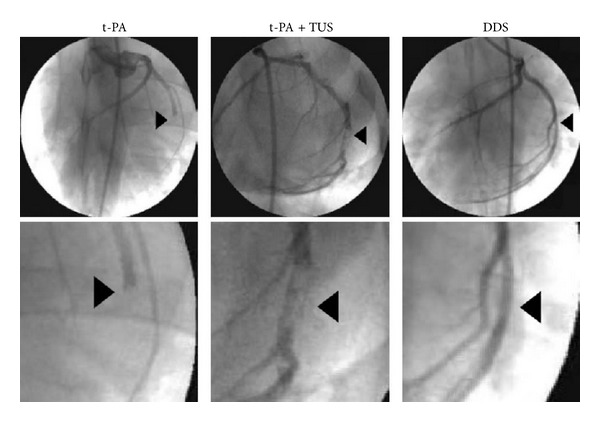

There are some exciting clinical applications of albumin, such as photodynamic therapy, transport protein for metal complexes, and an anti-HIV agent. Albumin bubbles can burst and release the drug after destruction by ultrasound. It can also be used as an artificial blood substitute with the development of tetraphenylporphyrinato-iron (II) bound to albumin. Human serum albumin (HSA) together with polyethylenimine (PEI) was formed as a nonviral gene delivery vehicle and tested for transfection efficiency in vitro. Spectrophotometric analysis was used to determine the stability and transfection efficiency was evaluated in cell culture using human embryonic epithelial kidney 293 cells. Optimal transfection efficiency was obtained when the particles were prepared at N/P ratios between 4.8 and 8.4. Kawata et al. [75] designed a novel nanosized delivery system of tissue-type plasminogen activator (t-PA) as a therapy to coronary thrombolysis; the results showed it had a suppressed thrombolytic activity of t-PA in acute myocardial infarction model after injecting of t-PA nanoparticles (25% t-PA, 55000 iu/kg) and would not increase the risk of bleeding but recovered the activity only under the action of ultrasound (1.0 MHz, 1.0 W/cm2) (Figure 7).

Figure 7.

Coronary angiography after thrombolysis. Typical coronary angiographic images at 60 min in swine treated with t-PA (55,000 IU/kg) alone, t-PA plus TUS, and DDS. The lower images are enlargements of each affected site. Arrowheads indicate the site of thrombotic occlusion before treatment [75].

With the development of nano-controlled release technology, ultrasound-mediated intelligent drug delivery system (DDS) has great prospect for the development of nanoscaled drug delivery system and acoustic trigger system. The system is mainly composed of the t-PA gene, basic gelatin, zinc ions (restrain activity of t-PA), and in vitro ultrasound. The ultrasound-mediated recovery of t-PA activity synergistically promotes the thrombolytic activity.